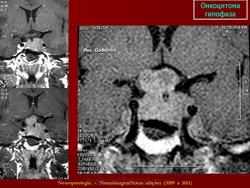

11. Онкоцитома.